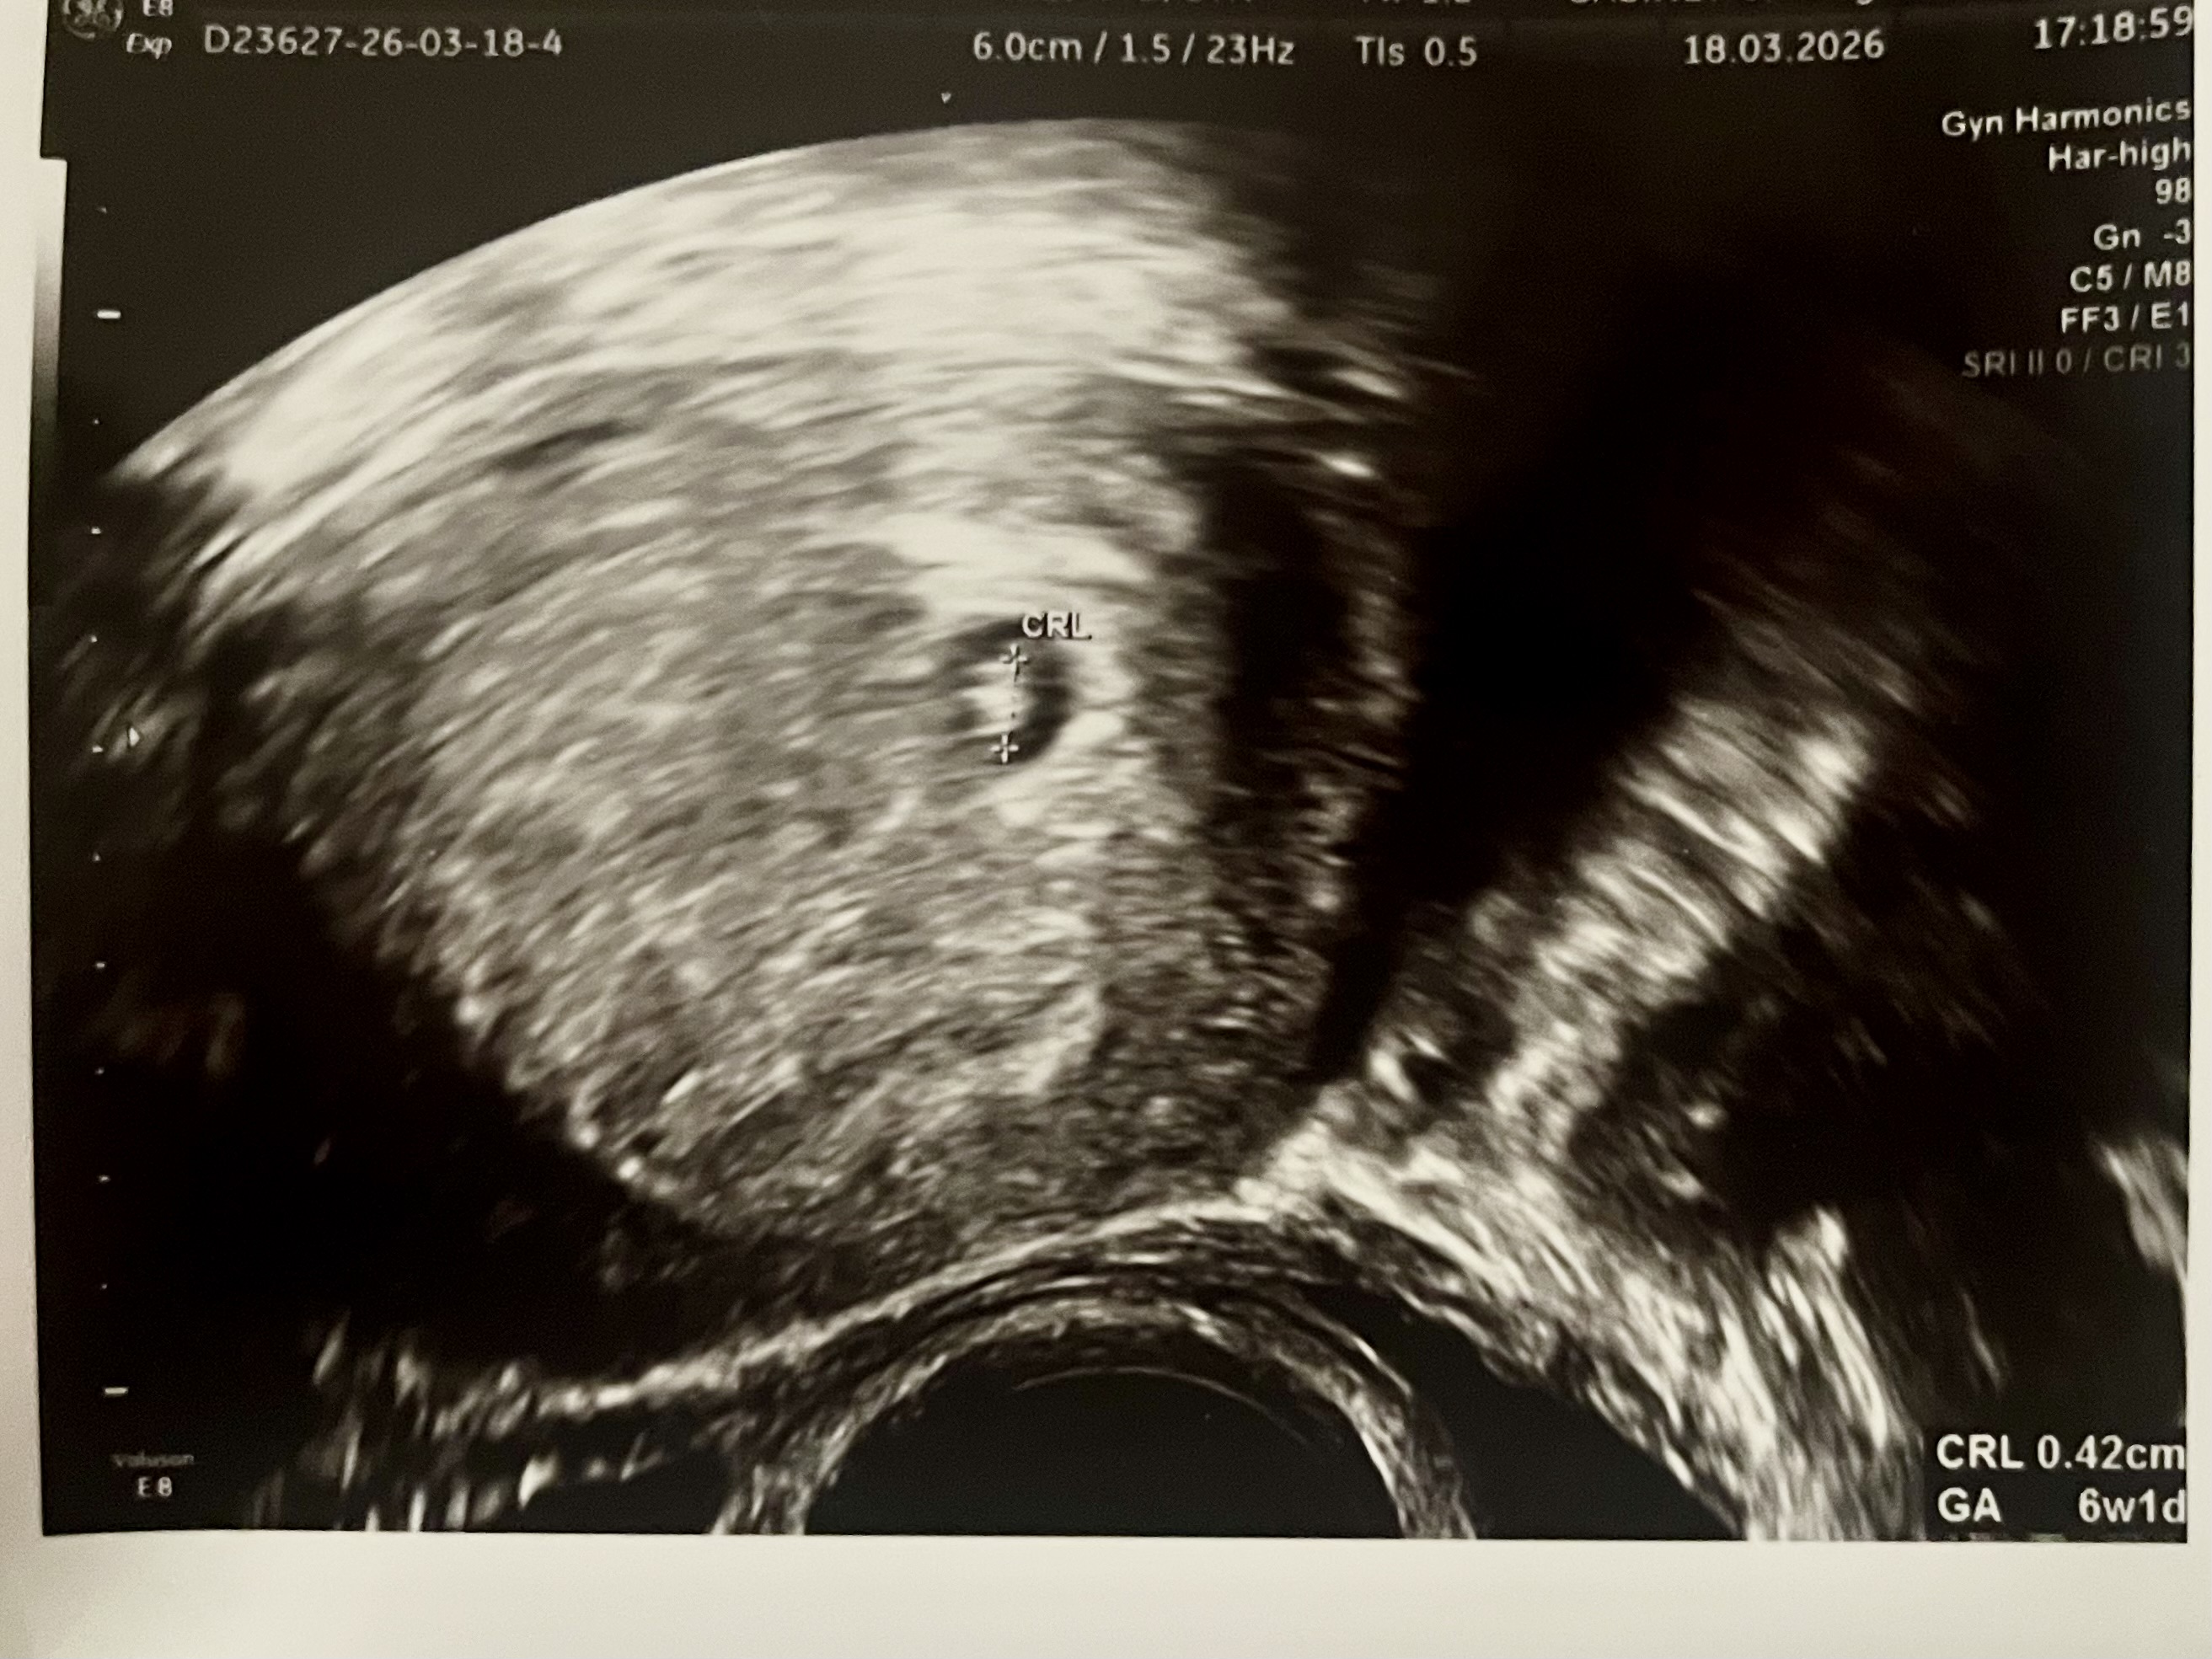

No i co jeszcze po wizycie - no mamy to 🥹 Jegomość bądź Jegomościna ma 4 mm 🥹 Z widocznym tętnem 🥹

IMG_6571.jpeg

Na dzień dzisiejszy jestem względnie spokojna, plamienia mam też obserwować, no i kolejna wizyta za 2 tyg. 🤪

Zobacz załącznik 1738107

Cudny obrazek. 🥰 Marzę o takim widoczku u siebie niebawem, mysle, że we wtorek to będzie nierealne ale może w kolejnym tygodniu. 🤞🏼